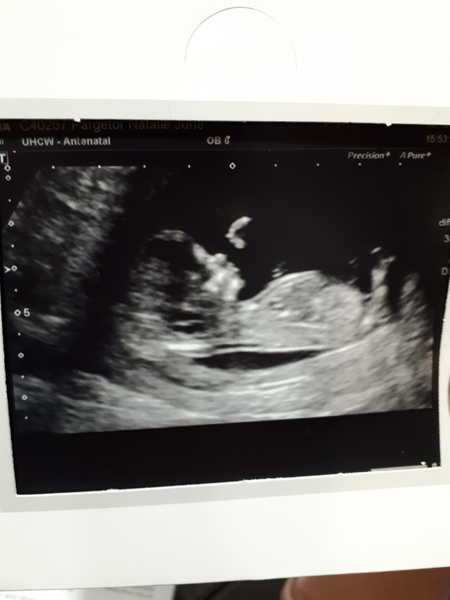

MigMog · 08/10/2018 13:03

Scan went super. Really clear chilled baby. Had to give it a wiggle to get it the right way around. Lush clear images too. Can't believe how much detail they can see.

Lovely scan pic MigMog :)

wit, migmog and shared, congrats on the lovely pics! Mine was today too, i was really not expecting all the movement: wiggling, twisting, waving and opening mouth like he was saying something! It was hilarious! They had a new machine so the sonographer was taking some extra time playing with the settings which was great as we had more time to sit mesmerized watching the screen! Saying that it was a new machine, the pic is not as clear as others but will try and attach.